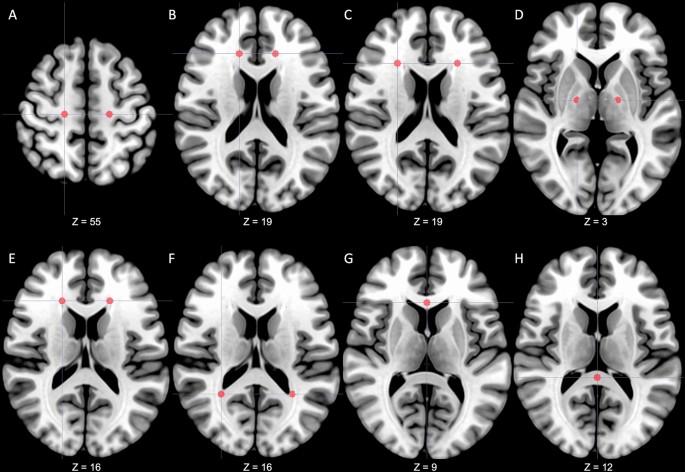

In this study, it was impossible to normalize DTI images into MNI (Montreal Neurological Institute) spaces due to the characteristics of patients with considerable brain deformity. Therefore, fourteen ROIs that showed significant differences in patients with iNPH were predetermined based on the results of previous studies9,25,26,32,41. Predetermined regions for ROIs were bilateral centrum semiovale, anterior and lateral areas of corona radiata, posterior limb of the internal capsule, periventricular white matter (PVWM) adjacent to anterior horns (area of anterior thalamic radiation) and posterior horns (area of inferior longitudinal fasciculus) of lateral ventricle, genu and splenium of the corpus callosum. (Fig. 2) The ROI masks were manually drawn using the AFNI (https://afni.nimh.nih.gov/) with a radius of 3 mm in three-dimensional space based on each patient's FA image and adjacent landmarks as references32,51. To ensure the objectivity of ROI selection, the MNI152 standard coordinates were first defined (Supplementary Table S3), and each ROI was selected by referring to the corresponding reference coordinates and surrounding anatomical landmarks in each patient's FA image. All ROIs were generated independently of clinical information by an investigator with five years (S Lee) of experience in neurology and double-checked for appropriateness by separate investigators (Y Lee and JW Kim). ROIs were exported to Image J (National Institutes of Health, Bethesda, USA) and applied to all DTI output files52. Right and left ROIs were analyzed separately.

Predetermined regions-of-interest. A total of 14 regions of interest were predetermined in the centrum semiovale (A), anterior area of corona radiata (B), lateral area of corona radiata (C), posterior limbs of the internal capsule (D), anterior horns of the lateral ventricle (E), posterior horns of the lateral ventricle (F), genu of corpus callosum (G) and splenium of corpus callosum (H). From a radiological perspective, the right side of the figure is the patient's left side. The z coordinate represents the position on the MNI152 standard template. MNI Montreal Neurological Institute.